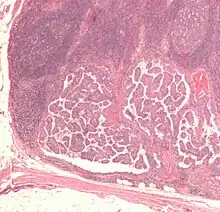

| 乳突狀甲狀腺癌的顯微鏡檢圖,可以看到癌細胞核呈現空亮狀,此特徵又稱為「安妮眼睛核 」,為此類型甲狀腺癌的重要病理特徵。 | |